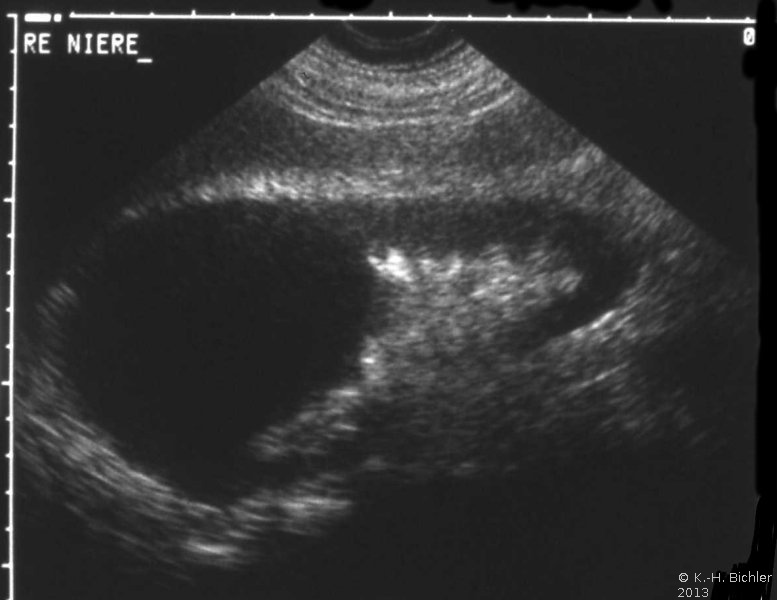

Diagnose und Behandlung von komplexen renalen Zysten bzw. unklaren Befunden umfassen eine Kombination von Sonographie, Urographie und CT (Abbildung 1). Dadurch soll eine Abgrenzung zwischen gutartigen und bösartigen Veränderungen erfolgen.